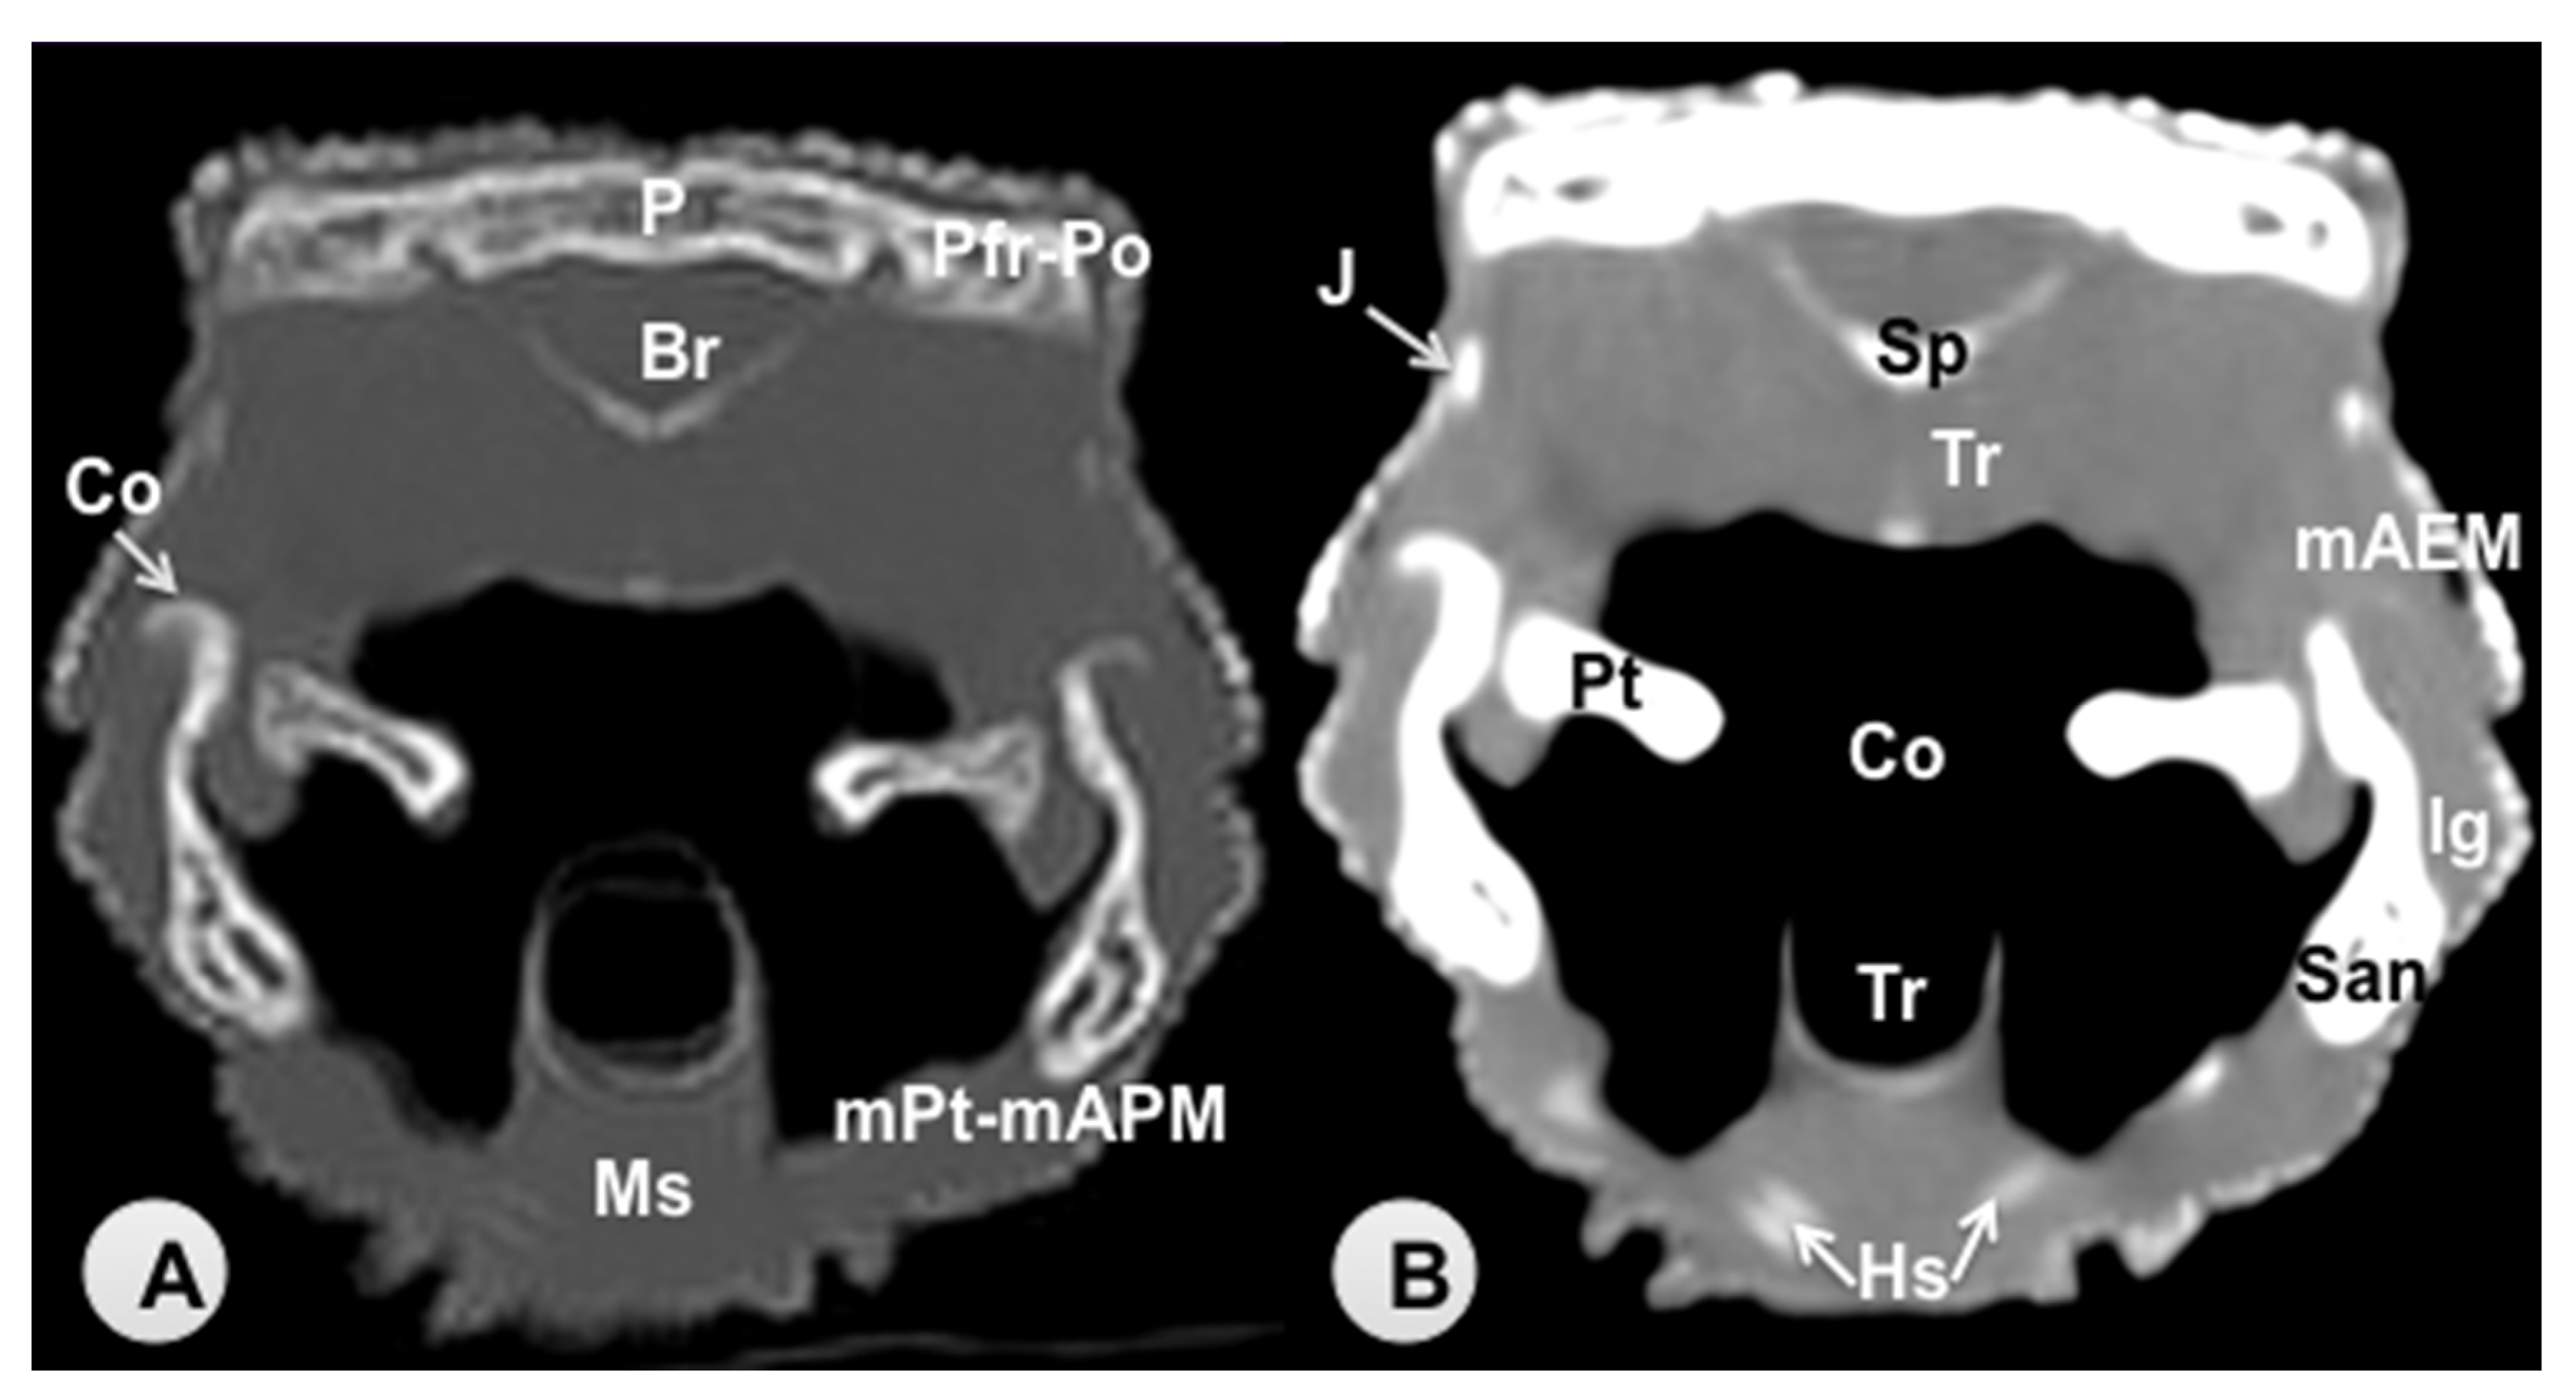

3.1. Transverse Computed Tomography Images